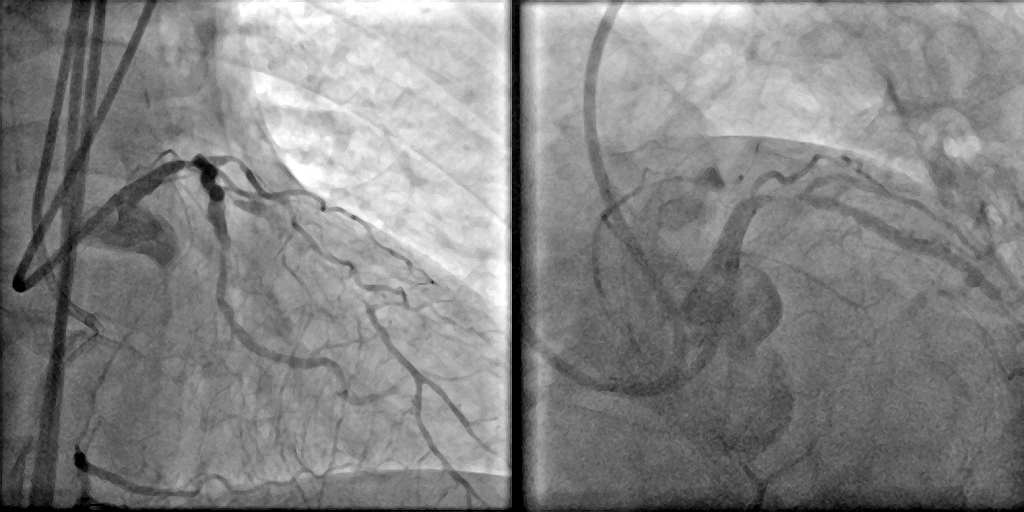

Coronary angiography demonstrated a right-dominant system with significant ostial LCx stenosis and a blunt ostial LAD chronic total occlusion, with a J-CTO score of 4. The RCA showed mild coronary disease and supplied collateral flow to the LAD territory, graded as Werner CC2.

Through bilateral femoral access, 7Fr EBU 3.5 and JR 4.0 catheters were engaged to the left main and RCA. With no antegrade entry, a retrograde marker wire and IVUS-guided antegrade puncture using Gaia Next 2 and Conquest Pro with Finecross failed, as both wires were deflected by the calcified cap despite tip modification with a secondary curve. A retrograde attempt using Gaia Next 2 and 3 with Finecross also failed.Suspecting LAD angulation, an antegrade re-attempt was performed using IVUS-guided puncture with a Conquest Pro 8-20 supported by a Supercross90 under retrograde wire guidance, successfully puncturing the proximal cap. Supercross was exchanged for Finecross, and the wire crossed distally, but Finecross and Corsair Pro XS could not advance due to the tight lesion. After proximal preparation and the anchor balloon technique in the LCx, the microcatheter advanced distally and the wire was exchanged for a workhorse wire. Retrograde injections confirmed true lumen position, and the LAD was predilated. IVUS showed mixed plaque and myocardial bridging in the mid LAD and mixed plaque at the ostial LCx. Further preparation was performed with a 3.5 mm scoring balloon. A hybrid strategy using a 4.0¡¿20 mm DCB for the LCx and a 4.0¡¿32 mm DES from LM to LAD, followed by 5.0 and 4.0 NC balloons for post-dilatation, achieved final TIMI 3 flow without complications.

This case demonstrates a complex left main bifurcation with a blunt ostial LAD CTO and tight ostial LCx stenosis, successfully managed through a hybrid strategy. When both antegrade and retrograde approaches failed, IVUS-guided puncture with a Supercross-supported high–tip-load wire enabled successful revascularization. The angulated microcatheter preserved the wire¡¯s penetration force, allowing puncture of the proximal cap. Procedural safety was enhanced by a retrograde marker and tip injection confirming distal cap position, while intravascular imaging provided the precision required for safe execution and optimal procedural outcomes.